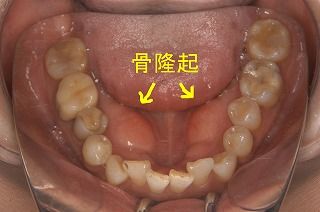

口の中が骨の隆起で話しづらくなって、舌のスペースを確保するために骨隆起切除術を昨年した。(参照:北山吉川歯科クリニックより 苦手な人は注意:グロ注意)

自分は心因性で寝ているときに歯を強く噛んでしまうため、眠るときにマウスピースをしているのだが、それ以前から強く噛んでいたため歯が沈んでしまい、その圧力で骨が変形して骨隆起になってしまった。で、以下の参考写真のように手術をしたのだが、本当に大変だった。(参照:歯科口腔外科塾より グロ注意)

骨隆起で悩んでいる方がいたら参考にして下さい。

以下のような手術工程でした。同じような症状のある方は手術の参考にして下さい。